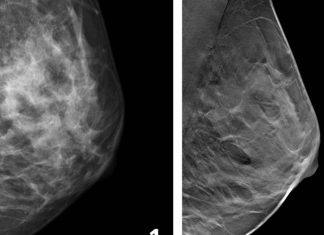

Study: Fewer breast cancer cases between screening rounds with 3D-mammography

3D-mammography reduces the number of breast cancer cases diagnosed in the period between routine screenings, when compared with traditional mammography, according to a large...